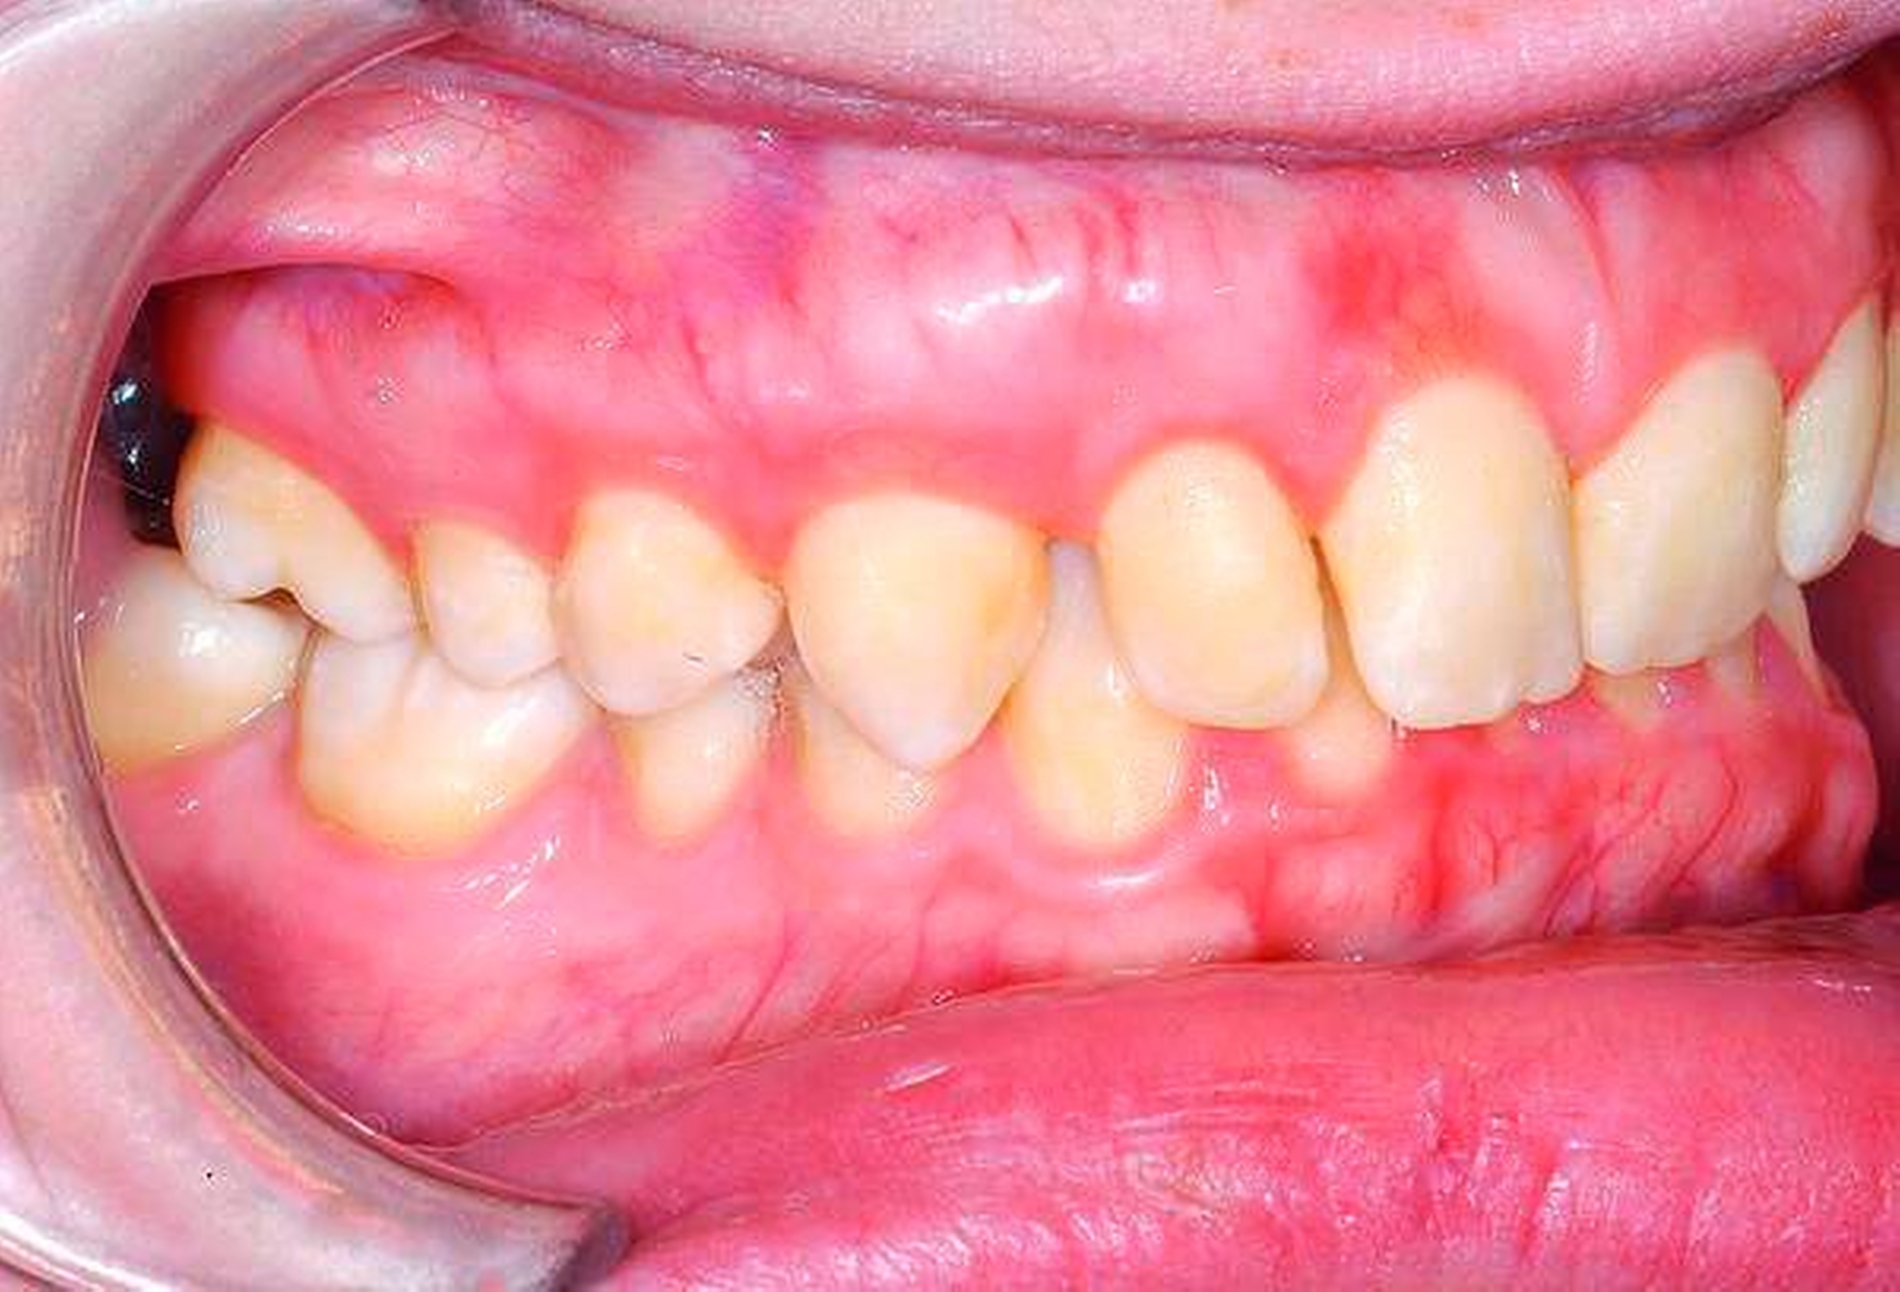

Die Entfernung aller Weisheitszähne wurde schließlich nach einem weiteren frustranen Extraktionsversuch unter Lokalanästhesie in Intubationsnarkose durchgeführt, der postoperative Verlauf gestaltete sich komplikationslos, auffällige Blutungen traten nicht auf (Abbildungen 2 und 3).